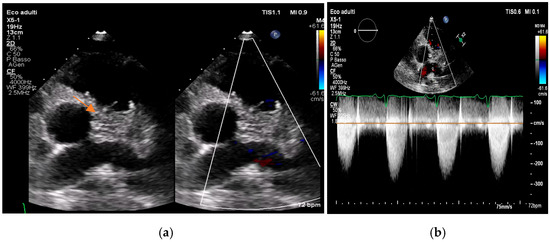

Multimodality Imaging in Infective Endocarditis: A Clinical Approach to Diagnosis

by Leonardo Brugiatelli, Francesca Patani, Carla Lofiego, Martina Benedetti, Irene Capodaglio, Pongetti Giulia, Francioni Matteo, Paolini Enrico, Nazziconi Marco, Kevin Maurizi, Furlani Giulia, Massari Arianna, Luciani Simone, Anselmi Benedetta, Gatti Chiara, Schicchi Nicolò, Fogante Marco, Tarsi Giovanni, Dello Russo Antonio, Di Eusanio Marco, Marini Marco and Fabio Vagnarelliadd Show full author list remove Hide full author list

Medicina 2025, 61(12), 2241; https://doi.org/10.3390/medicina61122241 - 18 Dec 2025

Infective endocarditis (IE) is a life-threatening condition with a rising incidence, demanding rapid and precise diagnosis. While echocardiography remains the cornerstone of initial evaluation, its limitations in complex cases—such as those involving prosthetic valves or cardiac devices—are well-known. This review synthesizes current evidence [...] Read more.

Infective endocarditis (IE) is a life-threatening condition with a rising incidence, demanding rapid and precise diagnosis. While echocardiography remains the cornerstone of initial evaluation, its limitations in complex cases—such as those involving prosthetic valves or cardiac devices—are well-known. This review synthesizes current evidence and guidelines to outline a practical, multimodality imaging approach for IE. We emphasize that integrating advanced techniques like cardiac computed tomography (CT) and [18F]-fluorodeoxyglucose positron emission tomography/computed tomography (FDG PET/CT) early in the diagnostic pathway, particularly in high-risk scenarios, significantly enhances diagnostic certainty, guides therapeutic decisions, and improves patient outcomes. A tailored imaging strategy, driven by clinical presentation and integrated within a multidisciplinary endocarditis team, is paramount for modern IE management. Full article

(This article belongs to the Special Issue Diagnosis and Treatment of Valvular Heart Diseases)

Show Figures

Figure 1